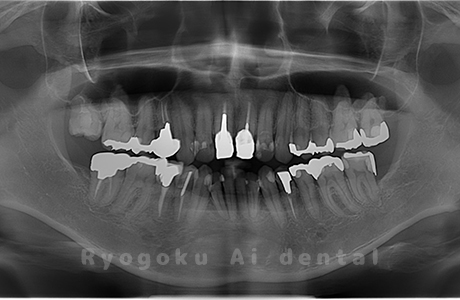

Case14

-

- 原因

- 重度カリエス、親知らず

- 治療内容

- 親知らずの抜歯、移植手術、マイクロエンド、ダイレクトボンディング

- 治療費用

- 220,000円

他院で親知らずと共に抜歯と診断された患者様です。親知らずの抜歯の必要性と左下奥歯の保存を試みた場合、歯の状態から根管治療、歯周外科、補綴の必要性から、移植治療を選択されました。大きな問題もなく、治療後も経過良好です。

<リスク・副作用>

治療後、痛みや違和感、出血、腫れなどが出る事があります。喫煙者、糖尿病などの方の場合、歯が生着しない場合があります。